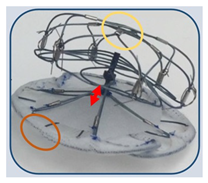

(Photo courtesy Occlutech International) | LAA Oclutech [82] Occlutech International | Self-expanding nitinol wire mesh with conical shape; distally attached loops and additional anchoring elements on flank; delivered via steerable guiding sheath allowing 180-degree rotation. | Distal loops penetrated LAA lobe in some animals; requires oversizing by 3–4 mm; learning curve for proper sizing and deployment. |